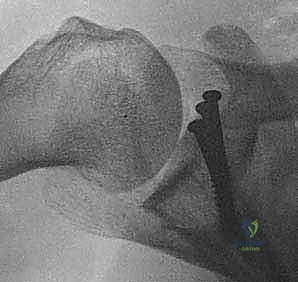

- الأشعة السينية (X-Rays): بأوضاع خاصة (مثل وضعية Stryker Notch و West Point) لرؤية الكسور العظمية المبدئية.

- الأشعة المقطعية ثلاثية الأبعاد (3D CT Scan): وهي المعيار الذهبي. يتم إعادة بناء صورة ثلاثية الأبعاد للكتف، مع طرح (إخفاء) رأس عظم العضد لرؤية التجويف الحقاني بوضوح تام، مما يسمح للدكتور هطيف بحساب نسبة الفقدان العظمي بدقة متناهية (بالملليمتر).

الشكل 5 • صورة مقطعية ثلاثية الأبعاد (3D CT) تظهر بوضوح التآكل الشديد والفقدان العظمي في الحافة الأمامية السفلية للتجويف الحقاني، مما يؤكد الحاجة الماسة للترقيع العظمي.